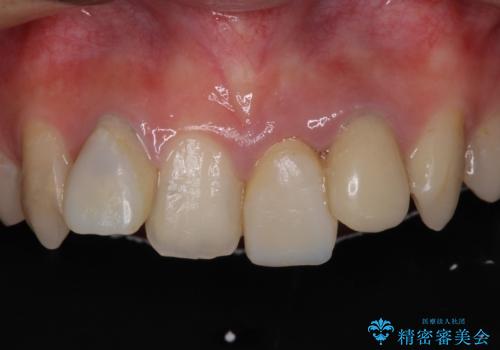

- 前歯のデコボコと、その結果むし歯が進行していることを気にして来院された患者様です。

前歯や奥歯の根管治療を行い、その後上下左右の第一小臼歯4本を抜歯してワイヤー装置にて矯正治療を行うこととしました。

矯正治療後には、根管治療を行った歯をオールセラミッククラウンにて補綴治療を行うこととしました。